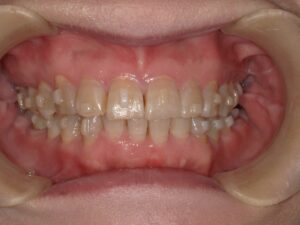

矯正治療

簡単に言うと、矯正力を使って前歯を骨の中にめり込ませる治療です。矯正用のインプラントと矯正用のゴムを用いて歯を押し下げます。期間は1〜2年程度が一般的です。この押し下げに用いる矯正力のコントロールが難しいです。また、ご自身でゴムを使ってもらわないといけないです。骨にめり込ませるというのは、指で歯を押し込むように力を加えていただくとわかると思いますが、骨の硬さにもよりますが難しいです。せいぜい1~2㎜くらいだと思ってもらうとよいかと思います。